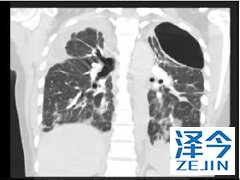

特发性肺纤维化的患者使用尼达尼布有收益吗 特发性肺纤维化属于间质性肺病中的一种,纤维细胞的不断增殖会对患者的呼吸造成影响,如果不进行及时的治疗,患者的平均生存期不会超过三年,而尼达尼布的作用就是在降低肺功能的基础上,缓解疾病的发展,为患者争取更长时间的无进展生存期。

尼达尼布在肺纤维化中的主要临床试验是INPULSIS-1和-2。1在这些试验中,共有638名患者随机接受150 mg 尼达尼布,每日两次,共52周,423名患者服用安慰剂。这些患者的强迫肺活量(FVC)至少是预测值的50%。在INPULSIS-1中,使用安慰剂,FVC下降了239.9 mL /年,使用尼达尼布下降了114.7 mL /年。INPULSIS-2的相应数字分别为207.3毫升/年和113.6毫升/年。使用尼达尼布的肺功能下降幅度较小,具有统计学意义。

在INPULSIS-1中,21%的患者因不良事件不得不停用尼达尼布。在两项试验中,超过60%的服用尼达尼布的患者出现腹泻,而安慰剂组的这一比例约为18%。与安慰剂相比,使用尼达尼布更常见的其他不良事件包括恶心,呕吐,体重减轻和肝酶升高。

虽然使用尼达尼布的过程中可能会出现副作用,不过相对于尼达尼布的治疗效果,副作用的出现也是可以被接受的。如果在经过治疗之后,比较严重的副作用还是得不到抑制,可能医生会考虑进行停药治疗。